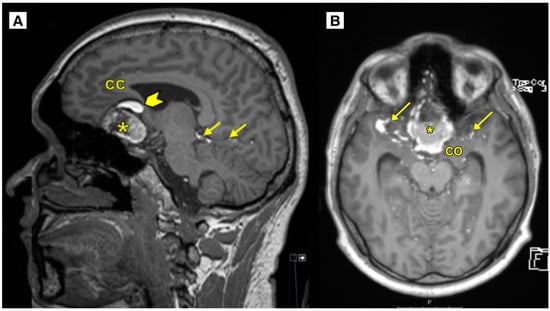

2.2. Imaging Findings